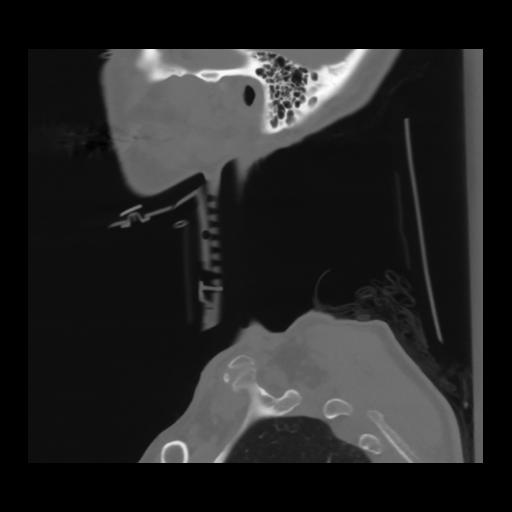

14 P.BLANDAS,,Sagittal,2.000,P.BLANDAS,Sagittal,